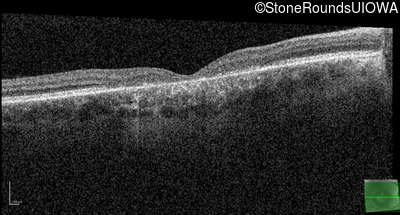

Age at visit: 17 years (Visit 2)

Age at visit: 21 years

Age at visit: 23 years

Age at visit: 25 years